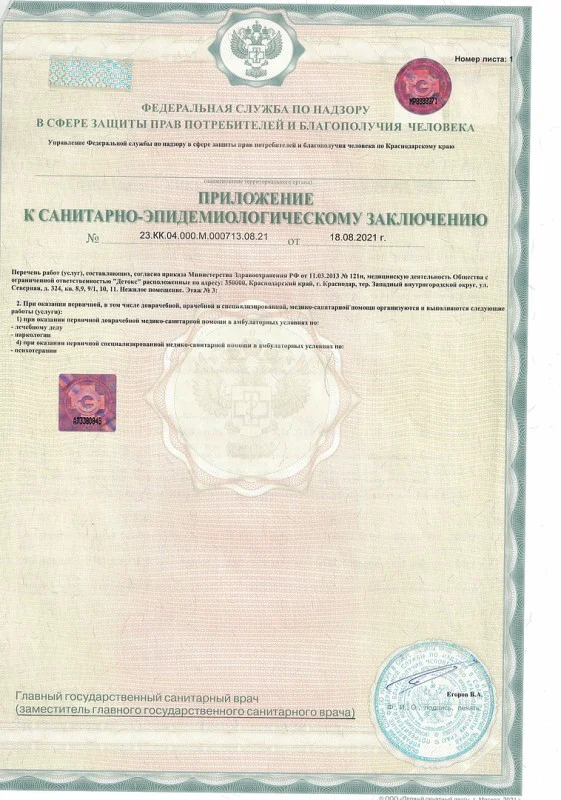

Лицензия на осуществление медицинской деятельности

Лицензия на осуществление медицинской деятельности

Лицензия на осуществление медицинской деятельности

Лицензия на осуществление медицинской деятельности

Лицензия на осуществление медицинской деятельности

Лицензия на осуществление медицинской деятельности

Лицензия на осуществление медицинской деятельности

Лицензия на осуществление медицинской деятельности